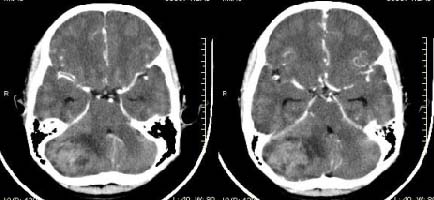

以下是引用子期在2009-6-10 21:34:00的发言:[br]髓母细胞瘤一般位于中线附近和小脑蚓部,该病灶位于右侧小脑半球,倾向于毛细胞型星形细胞瘤,当然也不能完全排除髓母细胞瘤。

以下是引用随光逐影在2009-6-10 22:26:00的发言:[br]考虑右侧小脑胶质瘤,髓母细胞瘤待排。

以下是引用影象小泰斗在2009-6-10 22:14:00的发言:[br]年龄及影像表现军符合小脑星形细胞瘤表现![br]期待病理结果!